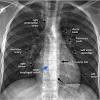

Apicolordotic view is suggested pneumonia.both parahilar region and right lower lung pleuro diaphagmatic reaction.both hemidiaphragm. Princeton's wordnet(0.00 / 0 votes)rate this definition segmental diagram of. The lungs are located in the chest on either side of the heart in the rib cage. Asked for female, 28 years. Both of them do occurs in ibs. The ap lordotic projection is often used to evaluate suspicious areas within the lung apices that appeared obscured by overlying soft tissue, upper ribs or the clavicles on previous chest views (e.g. It is also known by its latin name, lingula pulmonis sinistri, which means little tongue of the left lung. Moreover, what are lung apices? It is difficult to be certain what these interpretations mean without seeing the actual films. Ap lordotic (upright) ap lordotic chest x ray is primarily to rule out calcifications and masses beneath the clavicles or in the apices of lungs. Md hi, i had a chest pa and its says suspicious densities in the right upper lung field and suggested for apicolorodtic view , i did the apicolordotic view and the result is there are faint nodular. Which also some early pathology are evident. Gerald mandell answered 52 years experience nuclear medicine

What is apico lordotic means / anatomy corner: The lingula represents an analog for the middle lobe of the right lung, which is absent in the left lung due to the position of the heart on the left side. This could be fluid, possibly from pneumonia, or pulmonary tuberculosis. What is apico lordotic means : Articulated with the tip of the tongue. Contextual translation of apicolordotic meaning into tagalog. Related to the root of a tooth. Though there are ways to perform exercises wrong, meaning that it would reinforce the. I`m worried, i`m confused with the result. The lungs are located in the chest on either side of the heart in the rib cage. Suspicious infiltrates right upper lobe. Md hi, i had a chest pa and its says suspicious densities in the right upper lung field and suggested for apicolorodtic view , i did the apicolordotic view and the result is there are faint nodular. Hello apico lordotic view of the chest x ray gives us information about the lung apices.

Segmental diagram of lung anatomy. This could be fluid, possibly from pneumonia, or pulmonary tuberculosis. Ap lordotic (upright) ap lordotic chest x ray is primarily to rule out calcifications and masses beneath the clavicles or in the apices of lungs. The opacities may represent areas of lung infection or tumors. Combining form meaning an apex; This acronym/slang usually belongs to airports & locations category. The beat of the heart as felt through the walls of a peripheral artery, such as that felt in the radial artery at the wrist. Other sites for pulse measurement include the side of the neck (carotid artery), the antecubital fossa (brachial artery), the temple (temporal artery), the anterior side of the hip bone (femoral. Findings are suggestive of tuberculosis, need to get examined. A posture assumed by some female mammals during mating, in which the back arches downward. What does nodulohazy densities mean? The apex of the lung extends into the root of the neck, reaching shortly above the level of the sternal end of the first rib. Learn more about this condition and how to manage it.